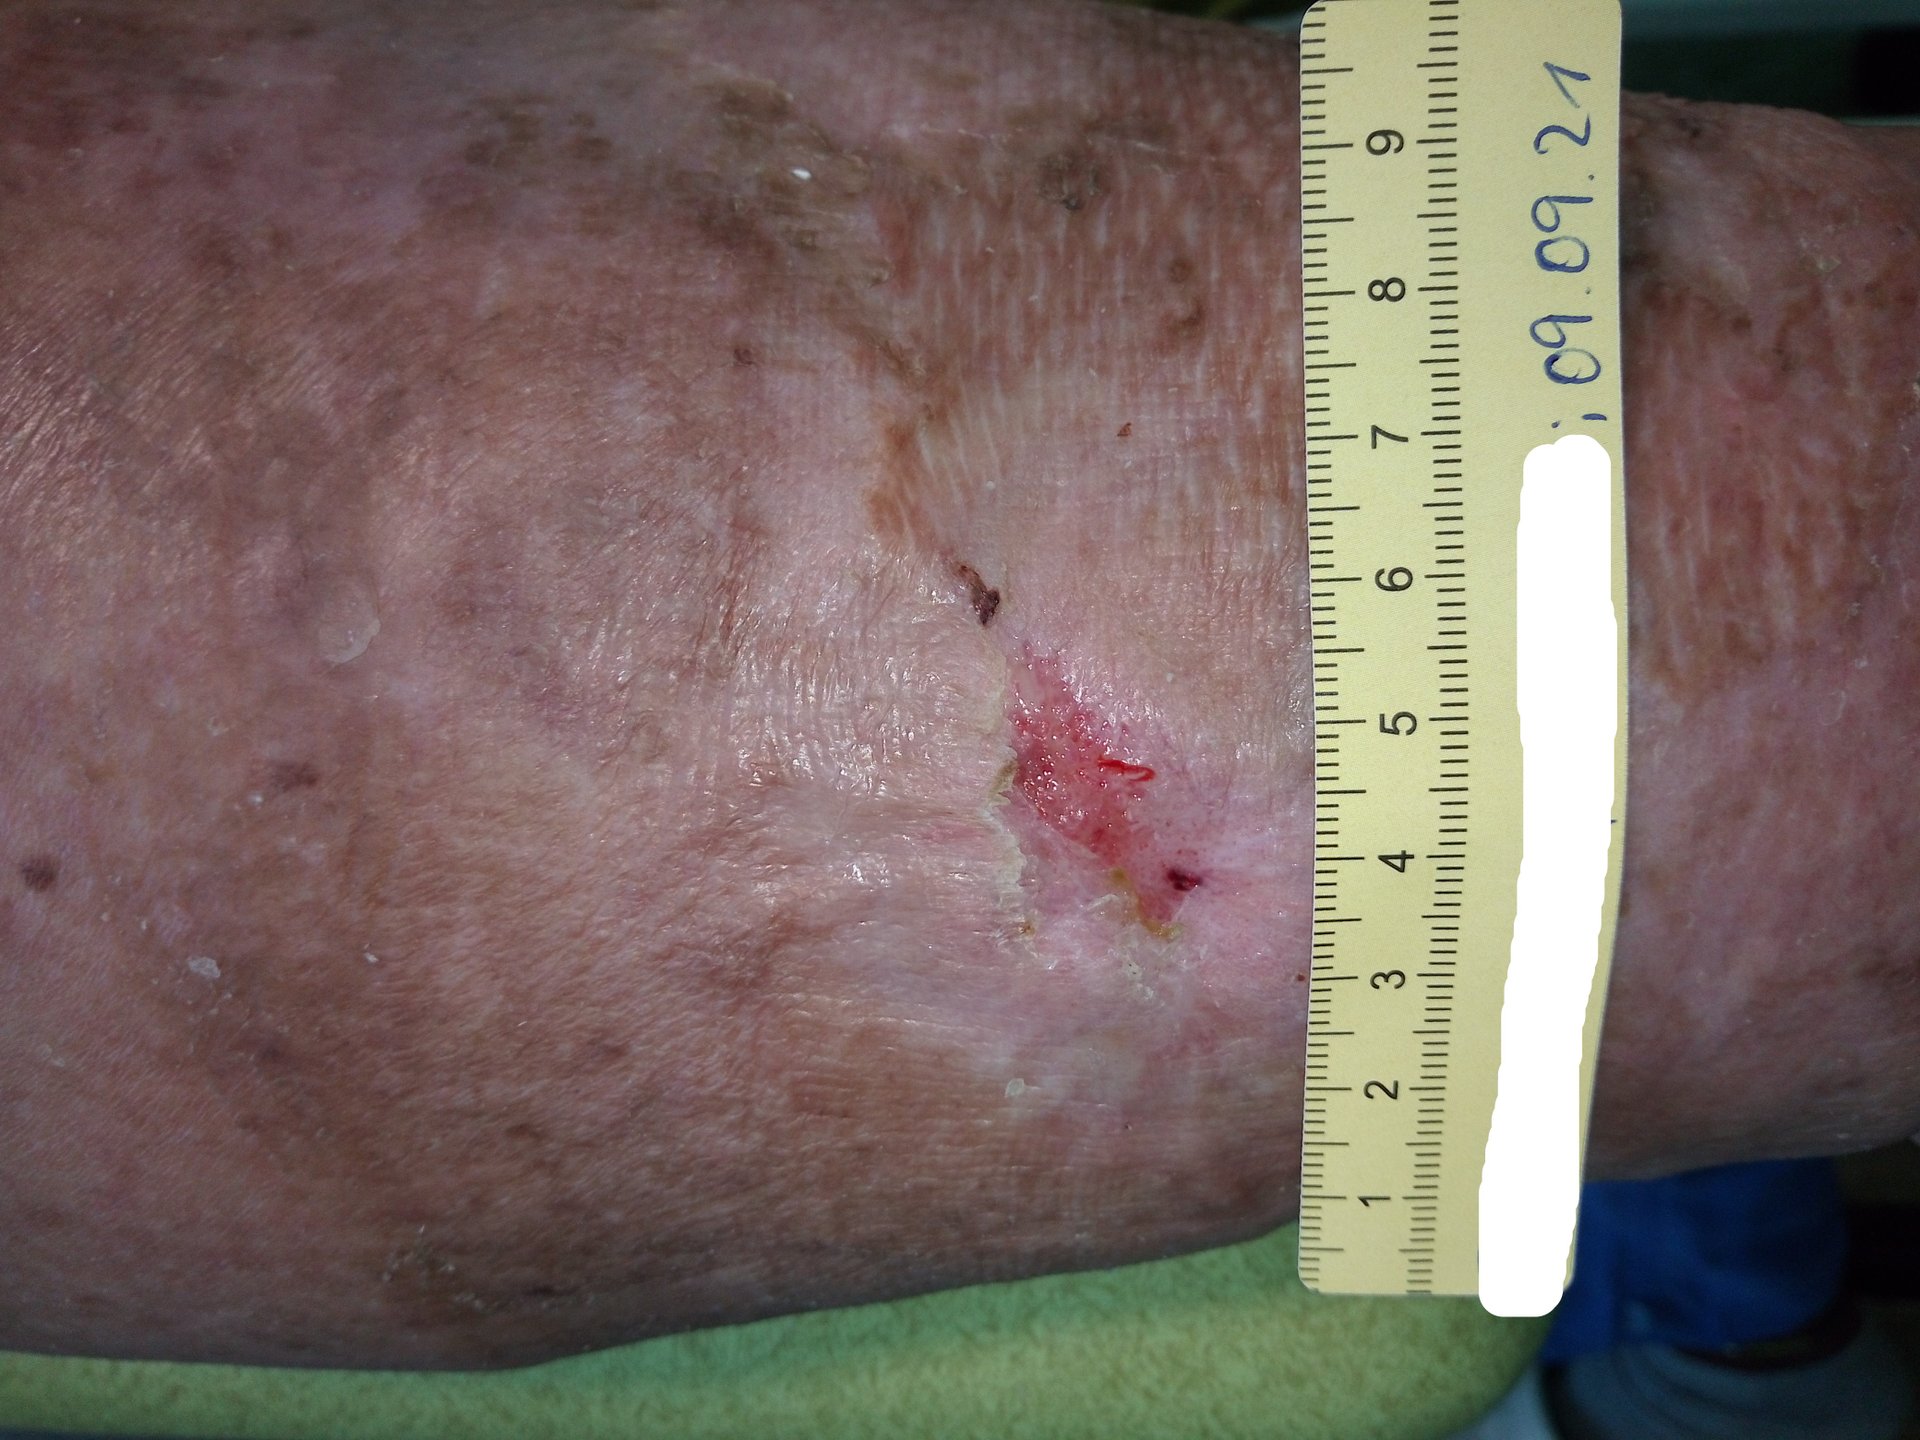

Bei der Erstvorstellung zeigte sich die Wunde mit einer Länge von 7,4 cm und einer Breite von 6,8 cm (Foto 1). Die Wundumgebung erschien durch Salbenreste, verklebt mit Hautschuppen und Exsudat, weißlich. Die Wunde sonderte viel gelblich-klares, seröses und geruchloses Exsudat ab. Der Wundgrund war überwiegend mit Fibrin und Biofilm bedeckt und der Wundrand zeigte sich stellenweise mazeriert. Die Umgebungshaut war sehr trocken und schuppig. Zudem zeigten sich ausgeprägte Ödeme, sodass ein Lymphtherapeut hinzugezogen wurde. Die Lymphdrainage erfolgte, ebenso wie der Verbandwechsel, alle 2 Tage.